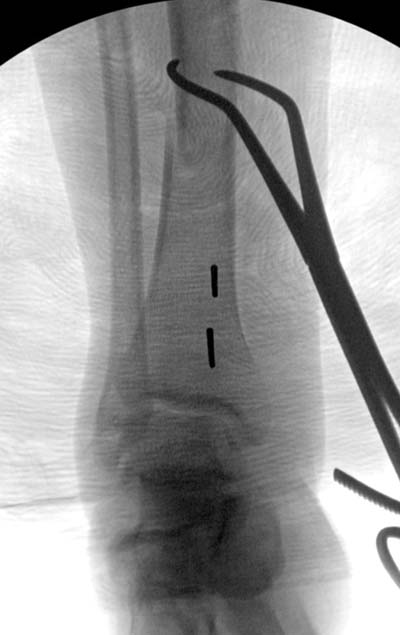

Здесь несколько снимков изолированного перелома большеберцовой с

интактной малоберцовой.  Weber clamp, блокирующие спицы и риминг в

центре канала отрепонировал перелом....